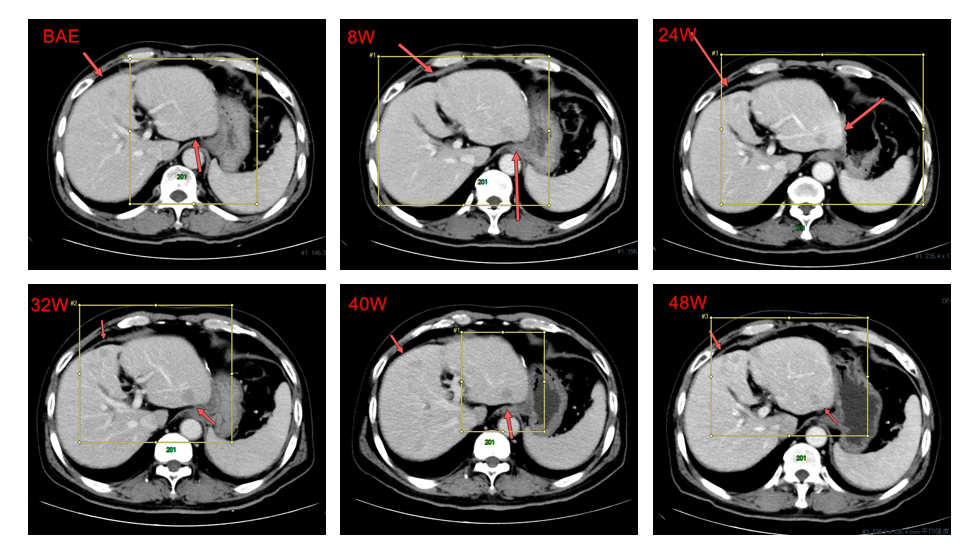

2016年4月13日,接受原发肝癌切除术,术程顺利。术后复查确认复发。2016年12月30日,首次服用多纳非尼(0.2g,每日两次)治疗,8周后经疗效评估为疾病稳定(SD)。随后继续使用,靶病灶持续稳定。经独立评审委员会(IRC)评估的无进展生存期(PFS)为7.5个月,而由研究者评估的PFS为11.2个月。

肝左叶非靶病灶影像学改变:8-24周为SD;32-48周为PD